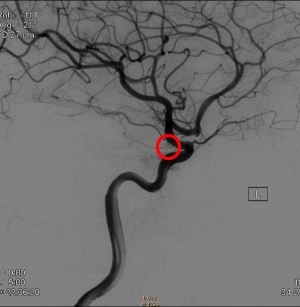

出国看病: 脑动脉瘤 严重吗?脑动脉瘤是大脑动脉上的一个薄弱部位,容易膨胀或充血。膨胀的动脉瘤会对神经或脑组织造成压力。它也可能爆裂或破裂,将血液溅到周围的组织中(称为...

脑动脉瘤 是常见的血管畸形。在大多数情况下,脑动脉瘤不会引起任何症状,也不会引起注意。在少见的情况下,脑动脉瘤破裂,释放血液到头骨,导致中风。 中国每年16万人死于...

脑动脉瘤 并非真的肿瘤,实际上属于一种血管畸形,因其外观类似于肿瘤而得名。颅内动脉瘤,病程隐匿,起病突然,一旦发病,致死率、致残率高,因而被称为颅内的不定时炸弹,是...